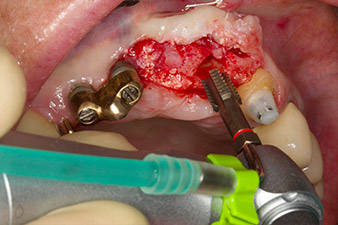

Following primary healing, the soft tissues were shaped using the basally lined bridge. Two months later the site was exposed by a slightly palatal alveolar ridge incision (Fig 2). The dimensions of the alveolar bone proved to be sufficient at position 22. Figures 2 and 4 show the preparation of the implant bed, the tapping and the implantation using Implantmed.

The new implantology motor was used with the appropriate W&H surgical contra-angle handpieces.

In order to compensate for the periodontal bone loss and achieve an aesthetically pleasing result, the implantation was combined with guided bone regeneration (GBR) with xenogenic replacement material and a collagen membrane

(Fig. 5 and 6).